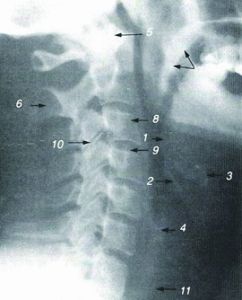

CT套用

CT診斷由於它的特殊診斷價值,已廣泛套用於臨床。但CT設備比較昂貴,檢查費用偏高,某些部位的檢查,診斷價值,尤其是定性診斷,還有一定限度,所以不宜將CT檢查視為常規診斷手段,應在了解其優勢的基礎上,合理的選擇套用。CT診斷套用於各系統疾病有以下特點及優勢,參考右圖。

CT檢查對中樞神經系統疾病的診斷價值較高,套用普遍。對顱內腫瘤、膿腫與肉芽腫、寄生蟲病、外傷性血腫與腦損傷、腦梗塞與腦出血以及椎管內腫瘤與椎間盤脫出等病診斷效果好,診斷較為可靠。因此,腦的X線造影除腦血管造影仍用以診斷顱內動脈瘤、血管發育異常和腦血管閉塞以及了解腦瘤的供血動脈以外,其他如氣腦、腦室造影等均已少用。螺鏇CT掃描,可以獲得比較精細和清晰的血管重建圖像,即CTA,而且可以做到三維實時顯示,有希望取代常規的腦血管造影。

CT對頭頸部疾病的診斷也很有價值。例如,對眶內占位病變、鼻竇早期癌、中耳小膽指瘤、聽骨破壞與脫位、內耳骨迷路的輕微破壞、耳先天發育異常以及鼻咽癌的早期發現等。但明顯病變,X線平片已可確診者則無需CT檢查。